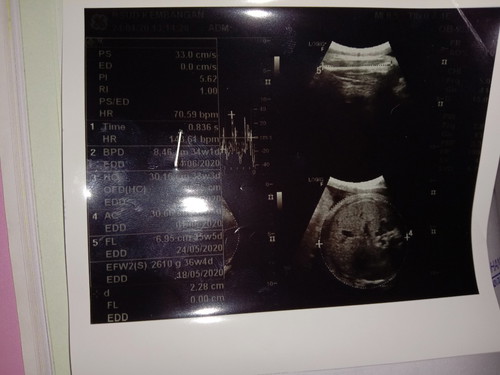

hsil usg 37w 4d

BPD lingkar kepala bayi, AC lingkar perut bayi, FL panjang tulang paha bayi, EDD tanggal perkiraan bayi lahir